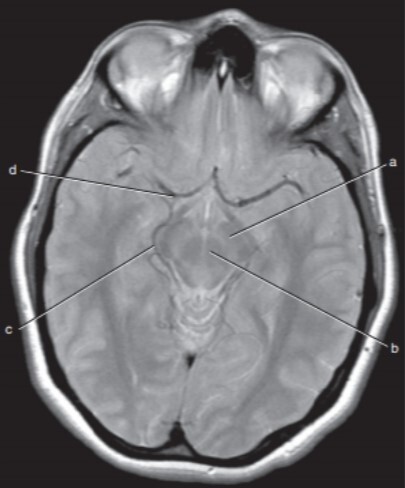

22

Q

Label a,c,d

A

a=Left cerebral peduncle (of Midbrain)

c=Right ambient cistern (with Rt posterior cerebral artery)

d=Right middle cerebral artery

23

Label a,b,c,d,f,g

a-Rt lateral fissure

b=Insula

c=Quadrigeminal cistern

d-3rd ventricle

f-Cerebellum

g=Anterior horn (of rt lateral ventricle)